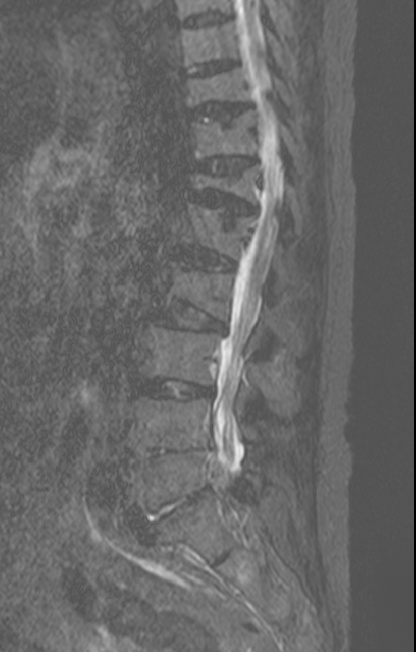

-L Spine MRI

-심한 과호흡 상태에서 검사 시행

-검사 도중 계속 움직임

-Motion Artipact 심하여 scan time 짧게 조정함.

- post L4-5 laminectomy

- flattening of T10 through L2 bodies with partially fatty bone marrow and some sclerotic change

- herniation of discs T10-11 through T12-L1 discs into adjacent vertebral bodies

- L2-3, L3-4 and L5-S1 diffuse bulging discs and ligamentum flavum thickening with indentation of thecal sac and encroachment on neural foramens

- some CSF effacement of L2-3 and L3-4 thecal sac

- partial to circumferential perineural fat effacement of left L5-S1 neural foramen

- decreased T2 signal intensity of discs with osteophytes

1. old T10 through L2 compression fracture with schmorl's nodes

2. L2-3, L3-4 and L5-S1 diffuse bulging discs

3. mild L2-3 and L3-4 central stenosis

4. moderate stenosis of left L5-S1 neural foramen

5. degenerative spondylosis